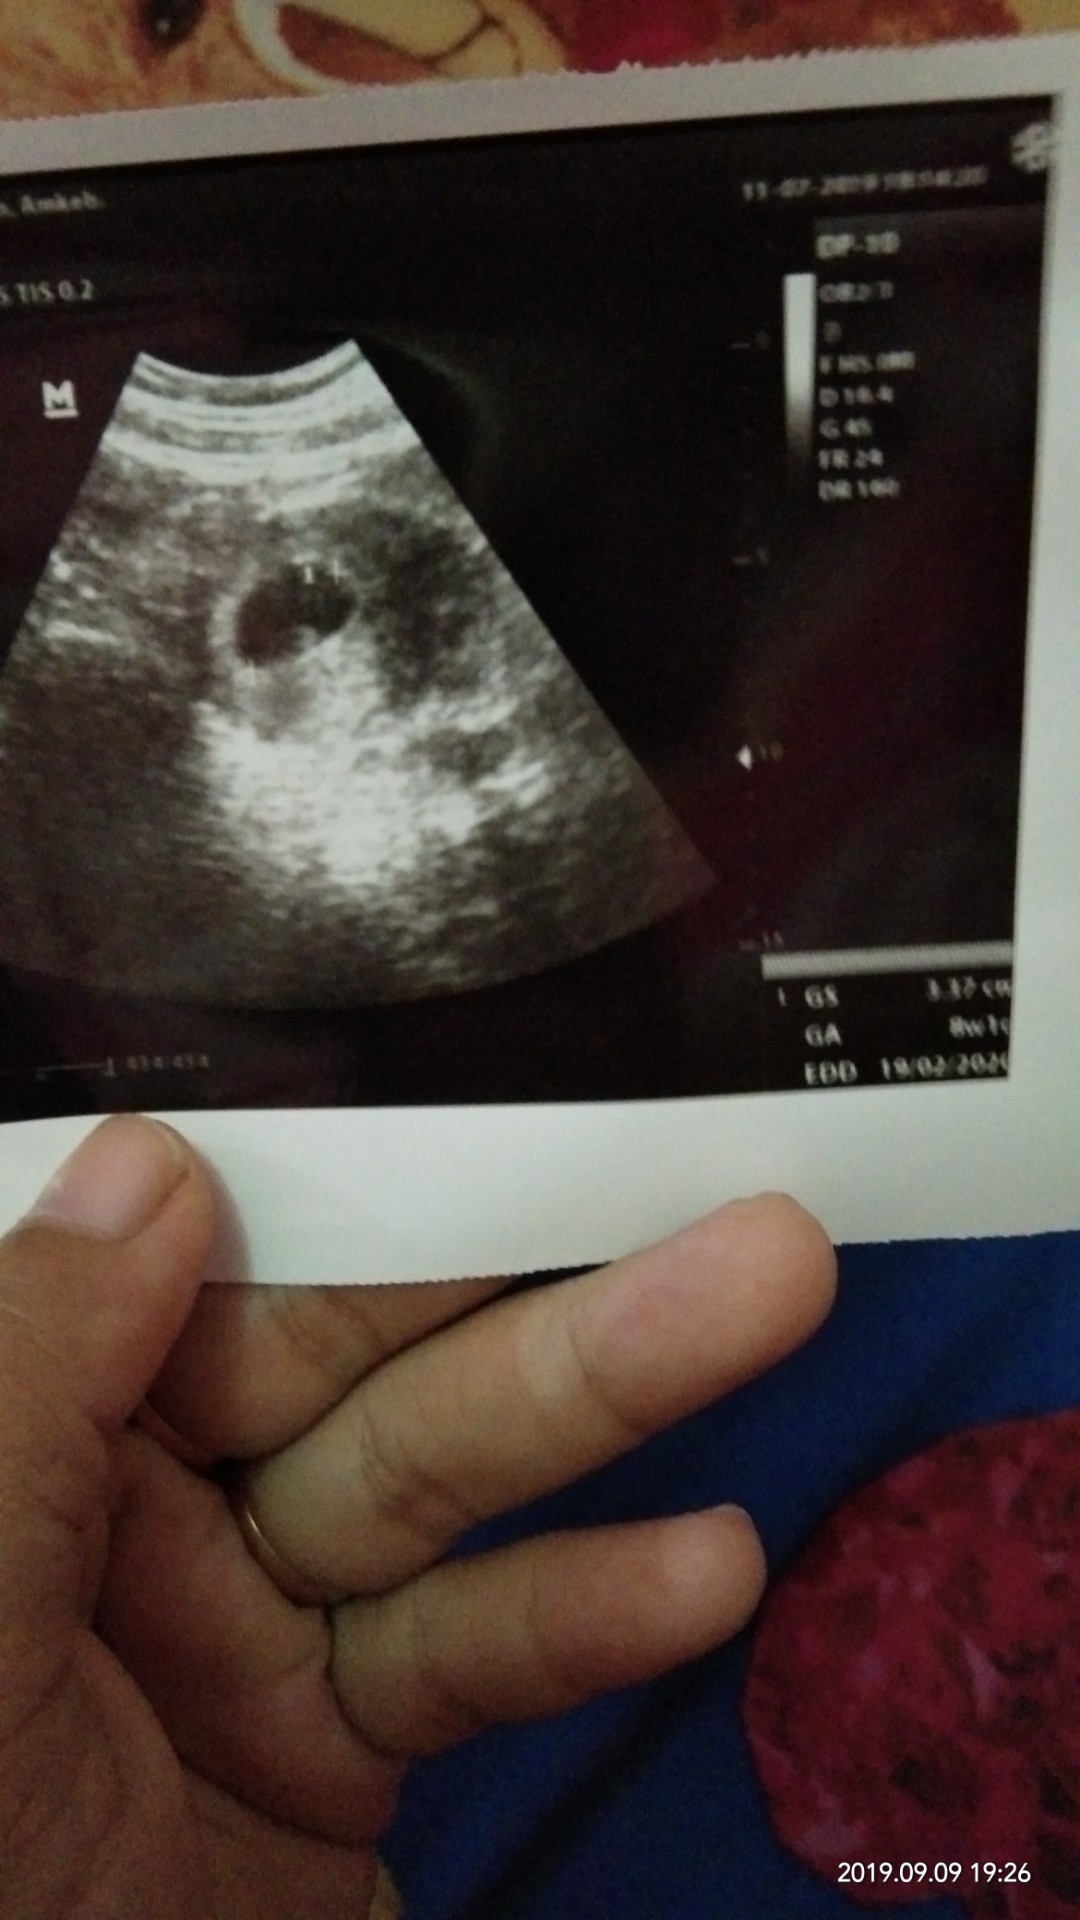

Ini usg saya waktu 8week masih kantung

Post reply image

itu yg putih di tengah bukan janin ya bun?

katanya normal nya udh hrs ada detak jantung bun.